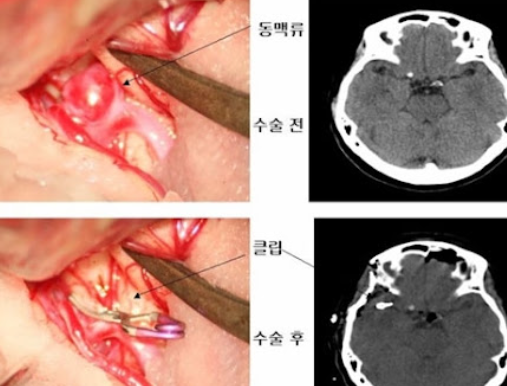

- 수술적 결찰술(Clipping)

- 머리뼈를 열고 동맥류의 목 부분을 금속 클립으로 집어 혈류가 들어가지 못하게 막는 방법입니다.

- 재발 가능성이 낮고 확실한 치료지만 개두술이 필요하다는 부담이 있습니다.